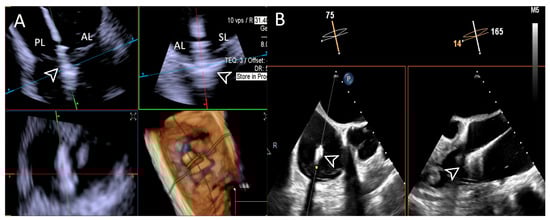

- Step number 5: clocking.

- Step number 6: grasping.